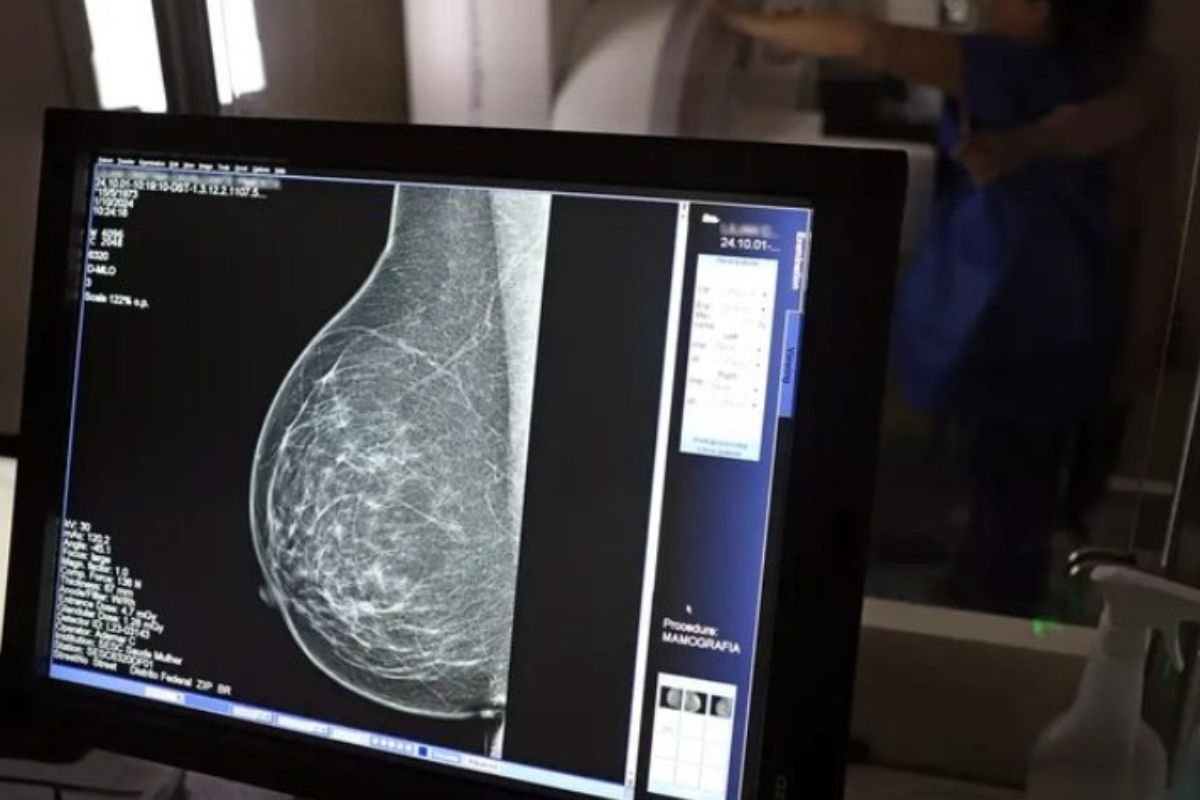

A mamografia no SUS passa a ser garantida para mulheres a partir dos 40 anos de idade. A medida está prevista na Lei nº 15.284, publicada no Diário Oficial da União desta sexta-feira (19), e amplia o acesso ao exame de forma preventiva em todo o país. Antes da mudança, o procedimento era oferecido de forma rotineira pelo Sistema Único de Saúde apenas para mulheres a partir dos 50 anos, salvo em casos especiais, como histórico familiar ou presença de sintomas.

Com a mudança, o exame de mamografia passa a ser garantido a todas as mulheres a partir dos 40 anos, conforme diretrizes do Ministério da Saúde, que também poderá estender o procedimento a outras faixas etárias.

A lei assegura o acesso à mamografia mesmo para mulheres sem sinais ou sintomas da doença. A faixa etária entre 40 e 49 anos concentra cerca de 23% dos casos de câncer de mama, e a detecção precoce aumenta significativamente as chances de cura.

Em 2024, o Sistema Único de Saúde realizou aproximadamente 4 milhões de mamografias de rastreamento e 376,7 mil exames diagnósticos. Os números reforçam a importância do rastreamento regular como estratégia fundamental para salvar vidas e garantir qualidade na atenção à saúde das mulheres.